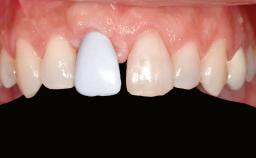

A 45-year-old woman with a completely edentulous maxilla was referred to evaluate the possibility of rehabilitation with an implant-supported prosthesis. This patient was healthy and a non-smoker. She had been wearing a maxillary complete denture opposing a natural mandibular dentition since her twenties. This situation had resulted in progressive resorption of the alveolar ridge, repeatedly creating a need for relining the denture. Twenty years later, despite multiple adaptations and the use of “glues” the denture was unstable and causing the patient psychological and functional discomfort.

| Provisional Implant-Supported Prosthesis | Prosthodontic margin < 3 mm apical to mucosal crest Prosthodontic margin < 3 mm apical to mucosal crest |